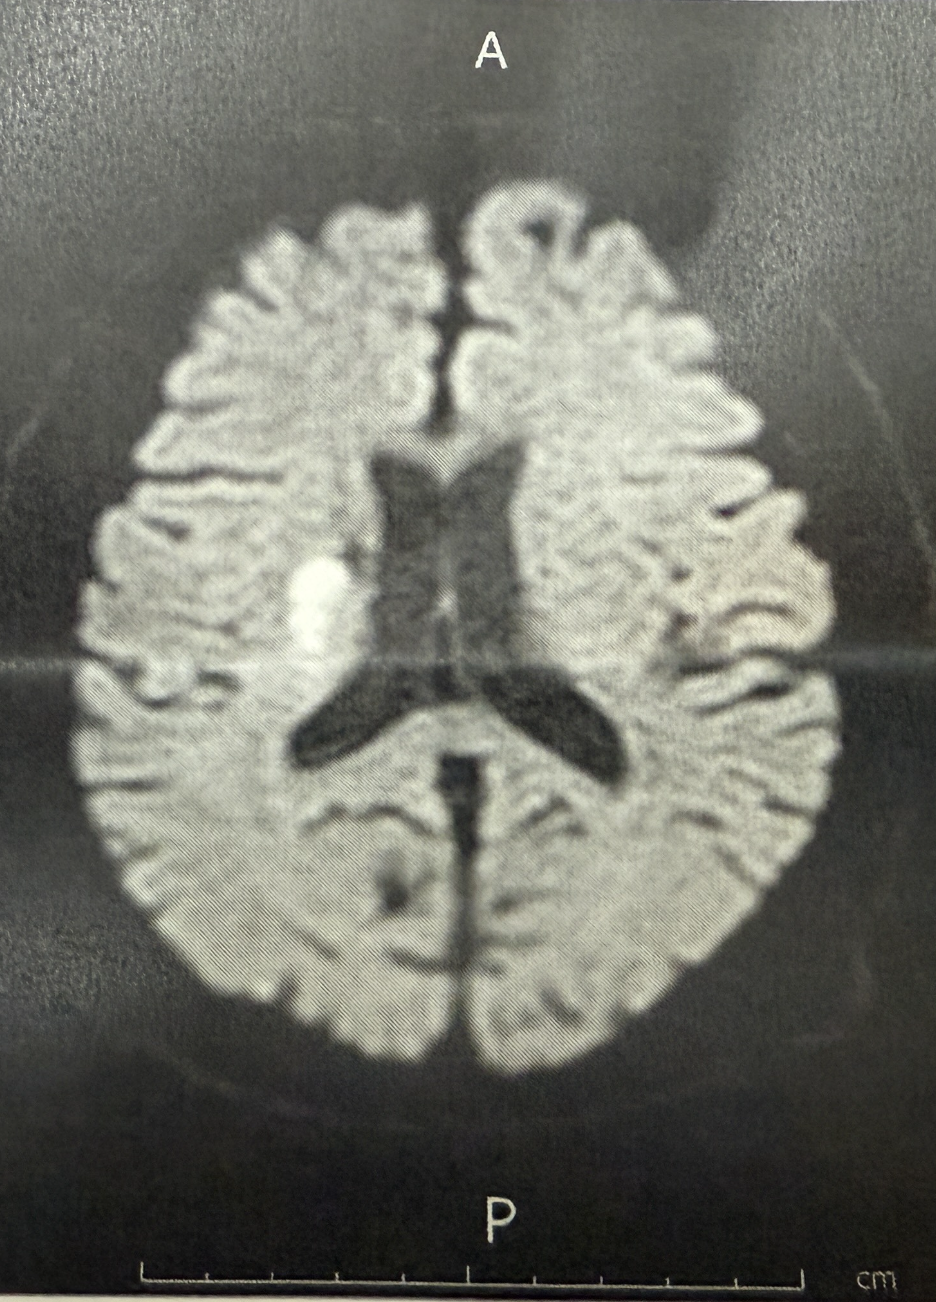

夫は「アテローム血栓症の脳梗塞」と診断され、2週間以内に再発する可能性があるそうです。